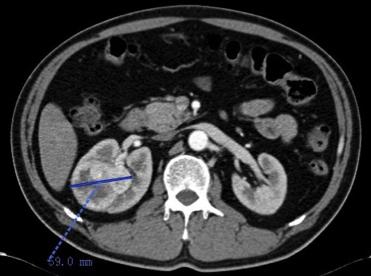

CT:右肾脏占位,可符合肾MT表现,请结合临床。肝脏富血供血管瘤可能,肝囊肿可能。

患者入院后完善相关检查,血生化检查发现肌酐水平高,且右肾肿瘤体积明显较左肾大,进一步同位素肾图检查发现左肾GFR 21ml/min,右肾GFR 47ml/min,若行右肾根治性切除,术后肾功能不全可能性大。遂经泌尿肿瘤多学科讨论后于2016.09.28行右肾肿瘤穿刺,穿刺病理:(右肾肿瘤,穿刺活检)倾向肾细胞癌,根据病理结果先行阿昔替尼5mg bid术前治疗。

2016.10.26复查肾脏CT:右肾MT较前缩小,肾包膜下少量积液(穿刺后改变),肝内血管瘤,肝小囊肿同前。

(治疗1月缩小到40mm)

右肾肿瘤最大径缩短从59mm缩小到33mm,缩小达44%,疗效评价PR。